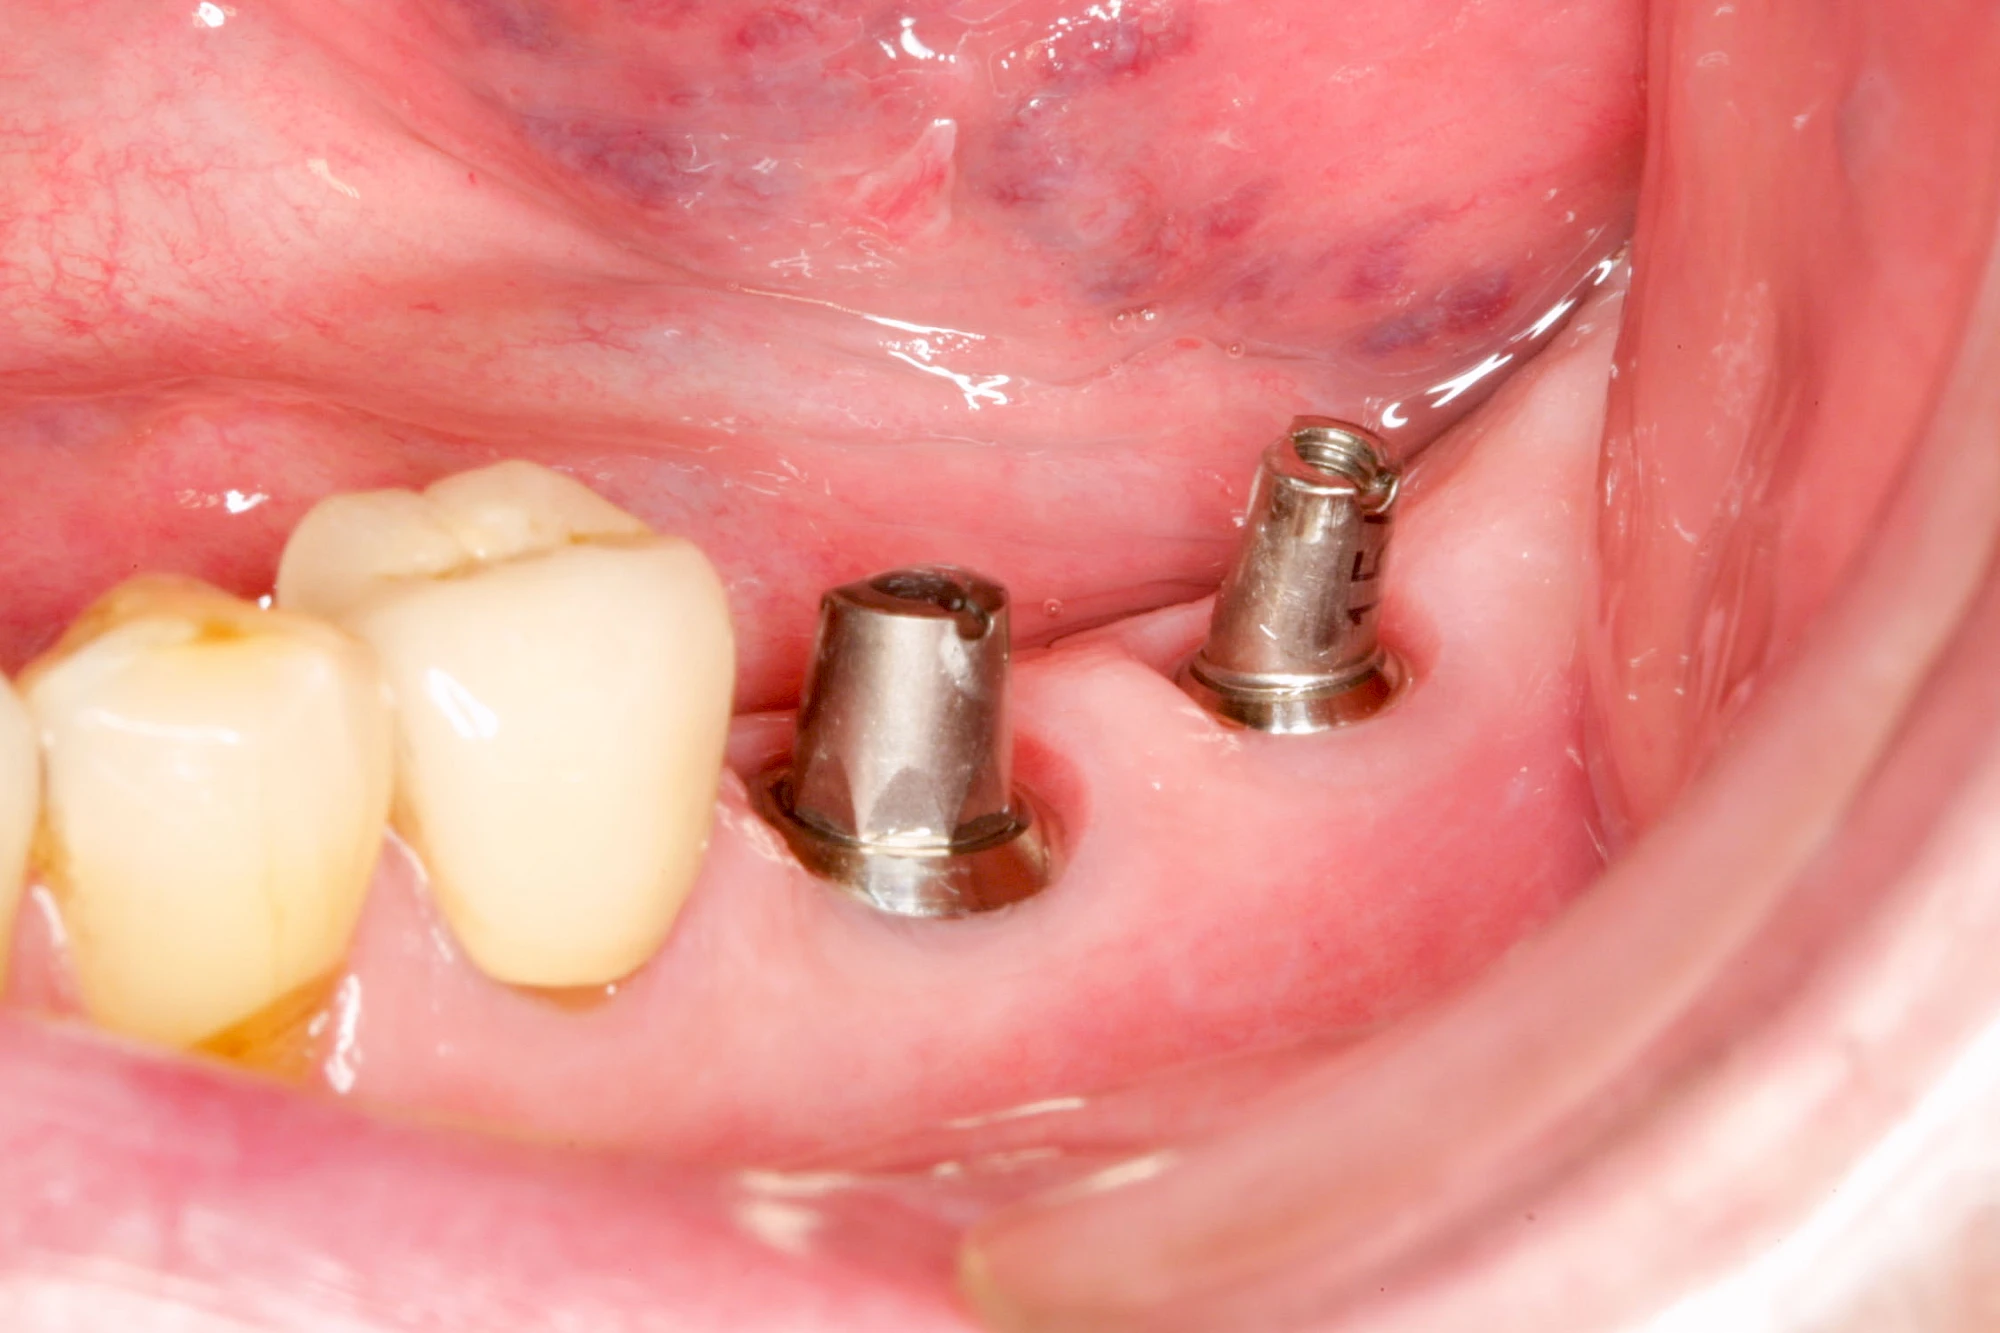

Implantate sind künstliche Zahnwurzeln. Nach einer gewissen Einheilzeit im Knochen (meist 3-6 Monate) erfolgt über einen separaten Aufbau (Abutment) die Befestigung einer Krone bzw. Brücke oder Zahnprothese.

In seltenen Fällen sind Implantate samt Aufbau aus einem Stück gefertigt. Auch gibt es Situationen, die ein Früh- oder sogar eine Sofortbelastung erlauben – dann kann die Einheilzeit der Implantate in den Knochen verkürzt oder sogar gänzlich darauf verzichtet werden.

Implantate: Bestandteile